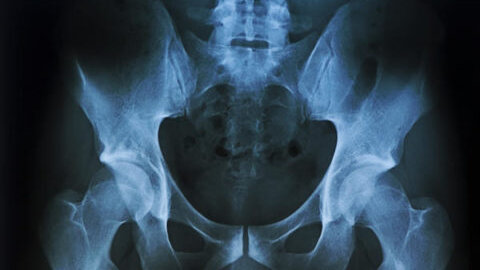

Тазобедренный сустав имеет сложное строение. Основной его составляющей является лонная кость, которая состоит из основного тела и двух, находящихся по обе стороны ветвей. Классификация переломов таза Повреждения тазовых костей можно разделить на 3 вида (на фото), рассмотренные в таблице: Основные типы перелома тазовых костейТипОписаниеСтабильный переломСмещение отломков не происходит, целостность тазового кольца не нарушается.Ротационно-нестабильные переломыПроявляются как результат воздействия боковых компрессионных или ротационных сил...

Тазовая кость, часть 2. Лонная кость.

Вторая составляющая тазовой кости. В её составе соединена неподвижно с подвздошной и седалищной костями. А посредством лонного симфиза (малоподвижное хрящевое соединение) соединяется с противоположной лонной костью. Формирует переднюю костную границу полости таза, переднюю стенку вертлужной впадины, верхнюю и нижнюю границу запирательного отверстия. Состоит из 3 основных частей - тела (которое формирует переднюю стенку вертлужной впадины), верхней и нижней ветви. На внешней части угла между ветвями...